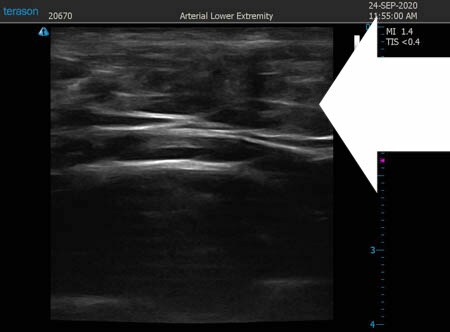

いつものように3Dタッチビュー(超音波)で

皮下脂肪層を評価してみましょう。

左肩甲骨横

↓ ↓ ↓

上の画像の部分の皮下脂肪層をつまんでみましょう。